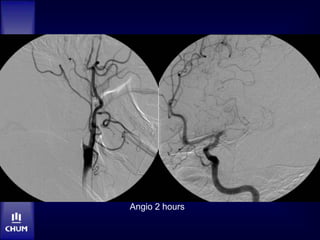

Case 2 – Mr. RD

HPI:

 19h17: witnessed sudden onset R hemiplegia,

speech arrest and fall. 911 called.

 19h27: ambulance arrival on site

 20h04: arrival at HND

 20h13: NCCT

 20h30: stroke team assessment

• Dysarthria, expressive aphasia, R hemiplegia

• NIHSS 13

 20h55: IV t-PA bolus, 2/3 dose

 21h05: Angio suite. No sedation.

Angio 2 hours

22h40: M1 recanalization